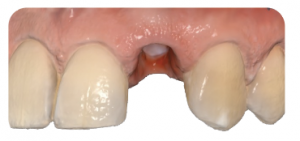

Module IV – Etapes cliniques

- Essayage des piliers

- Essayage des armatures

- Pose des couronnes DÉMONSTRATION CLINIQUE EN DIRECTE

- Prothèse supra-implantaire